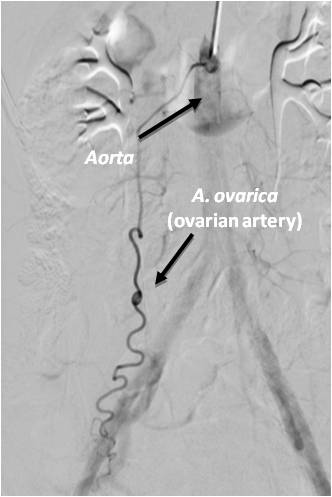

Fig. 6. A selective angiogram of the left ovarian artery supplying an interstitial-subserous uterine leiomyoma (an additional source of blood supply to uterine leiomyoma).

There are several types of communication between the uterine and ovarian arteries (Figures 7, 8); according to the literature, in patients with type 1 and type 3 anastomosis, a low clinical effect was recorded in 22% of cases, and in 5.2% it was completely absent [6]. Unfortunately, reliable identification of collateral vessels between the uterine and ovarian systems is very laborious angiographically and is not always possible before their expansion following embolization of the uterine arteries (Figure 9). For this reason, most authors recommend that the ovarian arteries be studied in the absence or insufficient clinical effect of the performed uterine artery embolization followed by their additional embolization in the long term [13]. Other collateral vessels from the cystic and internal pudendal arteries are not able to fully restore blood supply to myomatous nodules after embolization of the uterine arteries and have no clinical significance.

Fig. 7. A selective angiogram of the ovarian artery: utero-ovarian anastomosis type 1.

Fig. 8. A selective angiogram of the ovarian artery: utero-ovarian anastomosis type 2.

Fig. 9. A selective ovarian artery angiogram: blood supply to myoma through the left ovarian artery.

Isolated blood supply to uterine fibroids from the ovarian artery leads to the inefficiency of UAE in 3.2% of cases, it can be leveled out by endovascular intervention through the radial access and embolization of myoma through the ovarian artery.